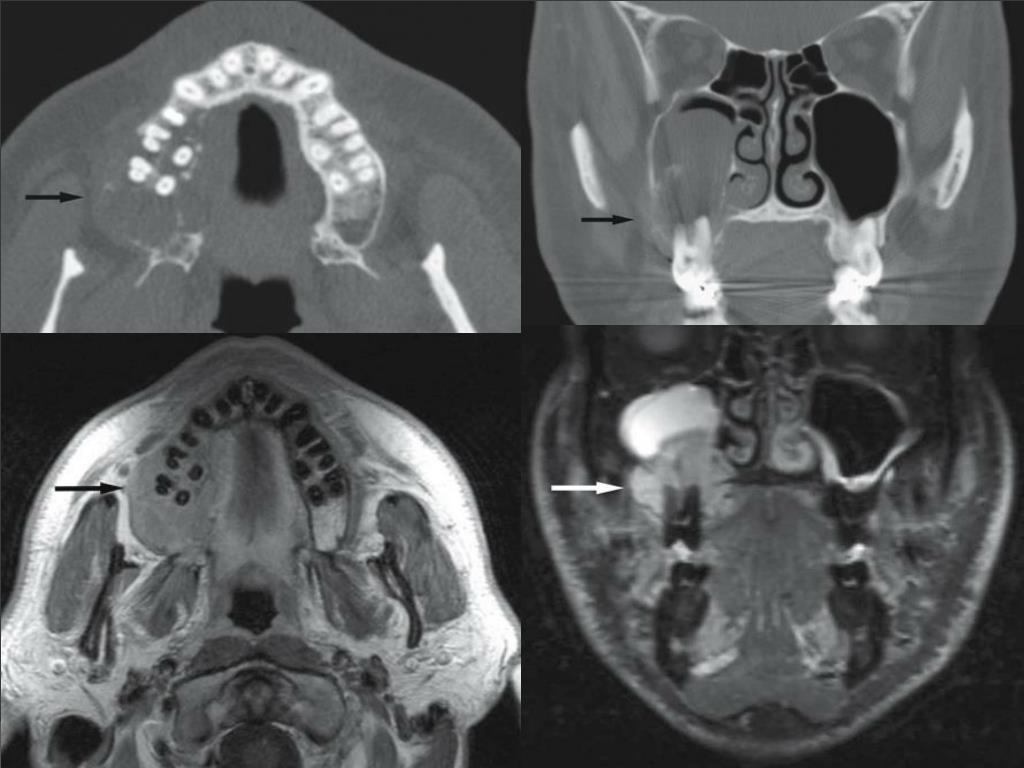

Imaging Characteristics of Benign, Malignant, and Infectious Jaw Malignant Tumor Jaw Bone Some malignant tumors that start in your jawbone, like osteosarcoma and primary intraosseous carcinoma, tend to be aggressive. Tumors that arise in the jaw can be either malignant or benign and are called odontogenic tumors. Six tumors will be covered in detail: Possible factors that might increase the. A person with jaw bone cancer develops a malignant tumor on their. Malignant Tumor Jaw Bone.

Imaging Characteristics of Benign, Malignant, and Infectious Jaw Malignant Tumor Jaw Bone Six tumors will be covered in detail: A person with jaw bone cancer develops a malignant tumor on their mandible, lower jaw bone, or maxilla, which is the hard palate or upper jaw bone. Tumors that arise in the jaw can be either malignant or benign and are called odontogenic tumors. Many types of tumors and cysts can form in. Malignant Tumor Jaw Bone.

Imaging Characteristics of Benign, Malignant, and Infectious Jaw Malignant Tumor Jaw Bone Six tumors will be covered in detail: The exact causes are not known. Tumors that arise in the jaw can be either malignant or benign and are called odontogenic tumors. Osteosarcoma, fibrous dysplasia, central giant cell granuloma, osteoma, osteochondroma, and osteoblastoma. Possible factors that might increase the. A person with jaw bone cancer develops a malignant tumor on their mandible,. Malignant Tumor Jaw Bone.

Imaging Characteristics of Benign, Malignant, and Infectious Jaw Malignant Tumor Jaw Bone Some malignant tumors that start in your jawbone, like osteosarcoma and primary intraosseous carcinoma, tend to be aggressive. Osteosarcoma, fibrous dysplasia, central giant cell granuloma, osteoma, osteochondroma, and osteoblastoma. Possible factors that might increase the. Six tumors will be covered in detail: Tumors that arise in the jaw can be either malignant or benign and are called odontogenic tumors. A. Malignant Tumor Jaw Bone.